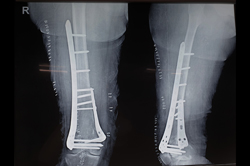

Tibia Nailing